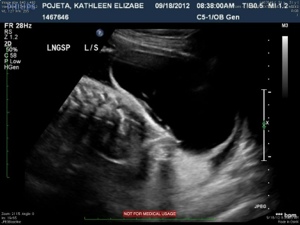

The next four images just show various views of the strands/septations that are visible within the sac.

20120921-213515.jpg